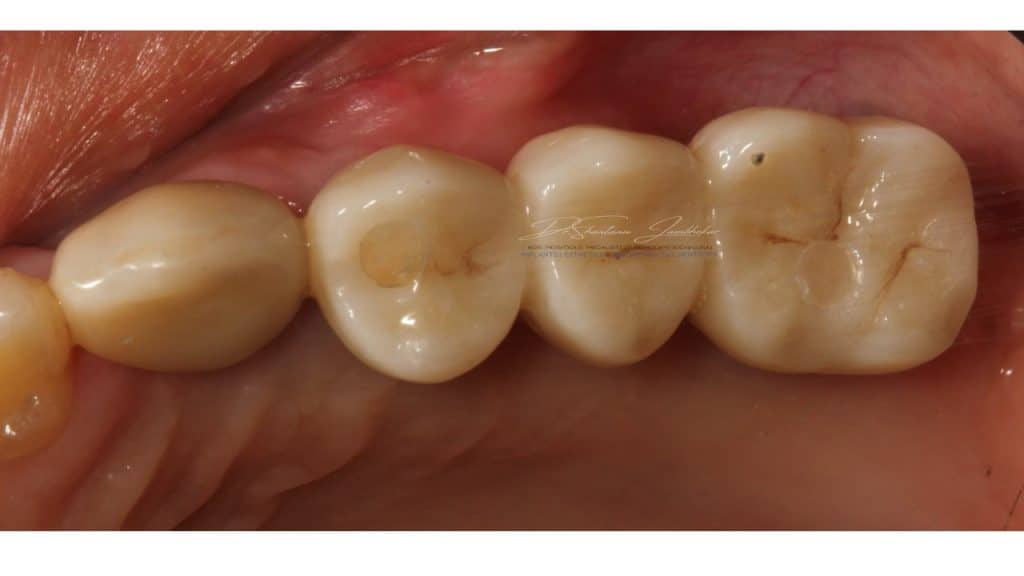

Cement retained Monolithic Zr Implant Restorations with 23 & Screw retained Monolithic Zr Implant restorations using Ti-base abutment with 24-25-26

Post treatment image at 12 months followup

Post Treatment Follow up at 22 months